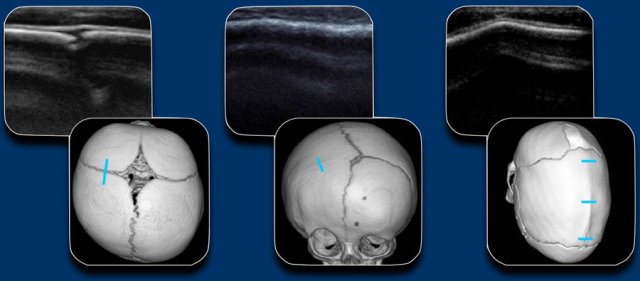

When a craniosynostosis is suspected, the first line imaging will be ultrasound or x-rays, depending on local expertise and preferences.

Because of lack of radiation, ultrasound is  the preferred method.

In case of high clinical suspicion low dose 3D CT is preferred.

The figure shows the US of a normal suture, an unilateral coronal stenosis and a sagittal stenosis with ridge.